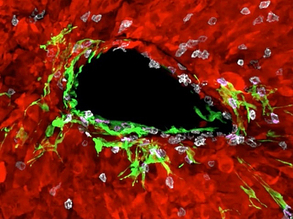

Abnormal Vessel